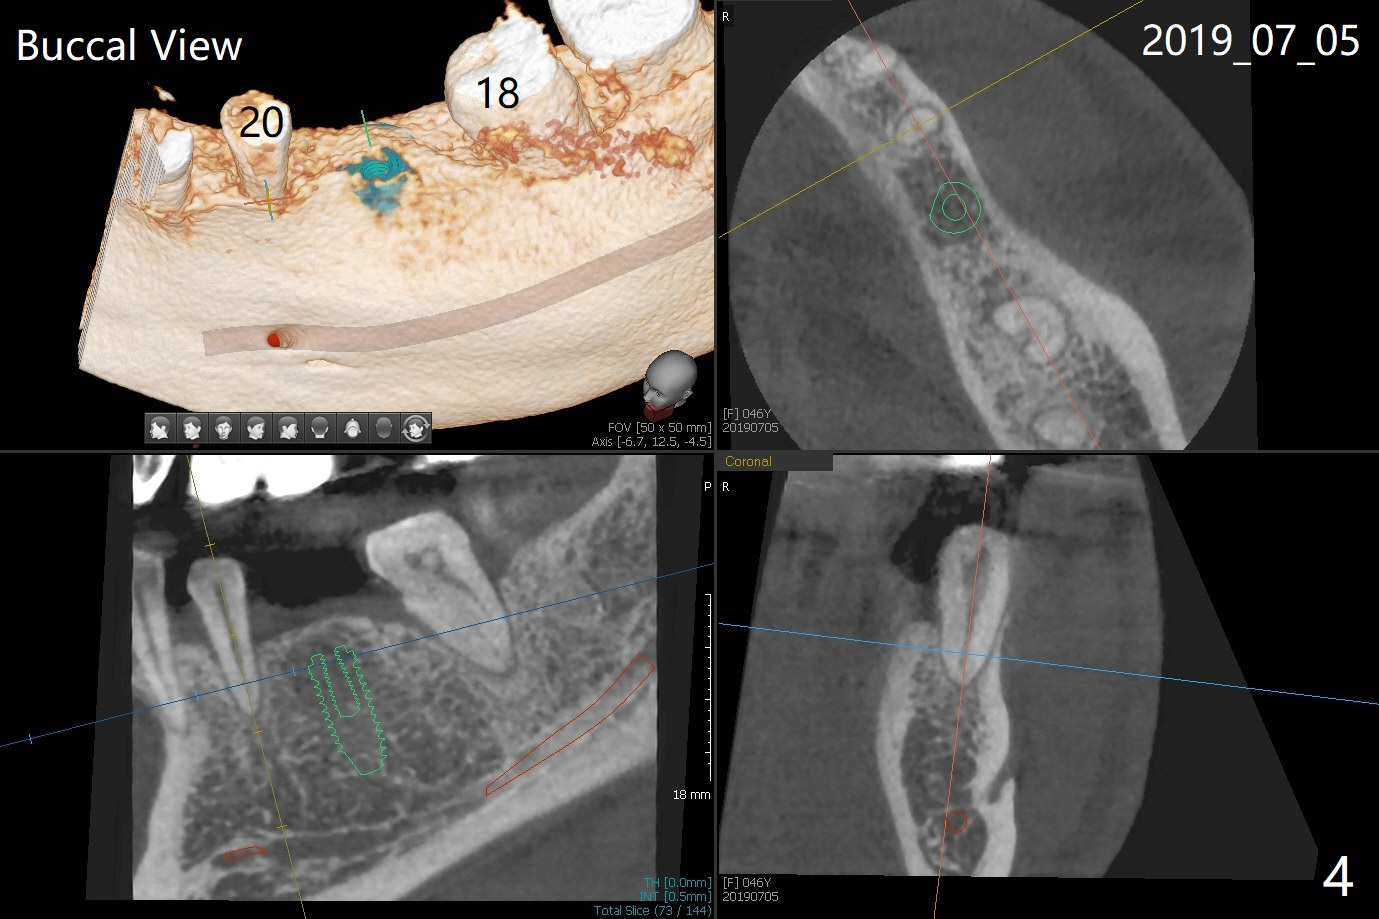

A 46-year-old woman had severe periodontal abscess lingual to #18-20 FPD a year ago (Fig.1,2 *). After SRP and Arestin placement #18 ML, the FPD was sectioned (Fig.2 >) to determine which abutment is to be extracted for implant. Since the sectioning, the patient has been unable to masticate on the left side (Fig.3). With removal of the FPD, CT is taken for surgical guide. Are the abutments salvageable (Fig.4,6)?